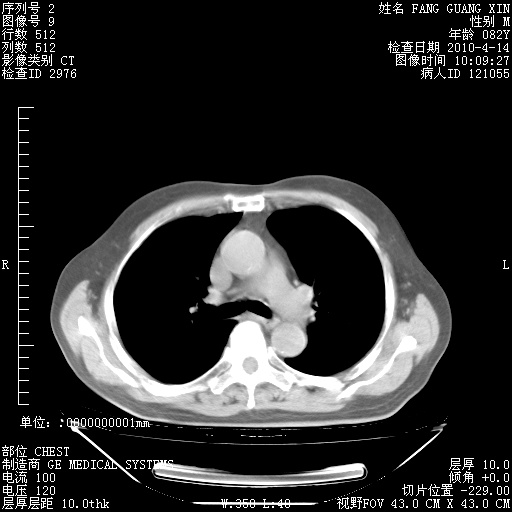

4月14日肺部CT